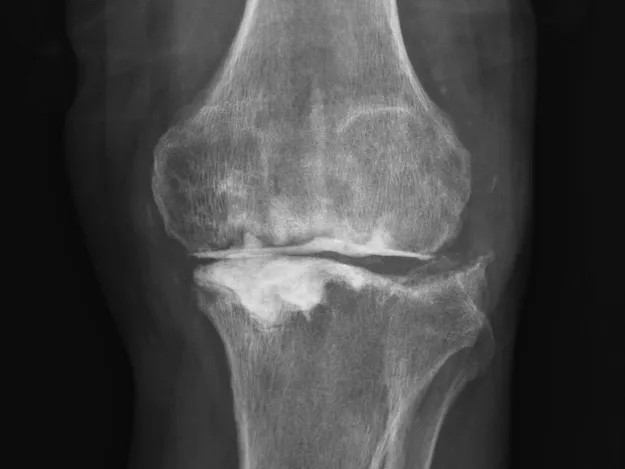

68歲的張先生(化名),本以為一次膝關(guān)節(jié)單髁置換手術(shù)能終結(jié)他的疼痛。然而,術(shù)后感染不期而至,將他的生活拖入長達8個月的灰暗期。

膝關(guān)節(jié)持續(xù)紅腫、疼痛,每一步都伴隨著不適與恐懼。反復(fù)治療,效果卻不盡如人意。傳統(tǒng)手段面對此類術(shù)后感染、結(jié)構(gòu)遭破壞的復(fù)雜局面,往往力不從心,患者可能需要經(jīng)歷多次手術(shù),且功能恢復(fù)難以保障。

清創(chuàng)只是第一步,如何在一片“復(fù)雜地形”中重建一個穩(wěn)定、功能良好的膝關(guān)節(jié),是更大的挑戰(zhàn)。為此,團隊引入了計算機輔助手術(shù)規(guī)劃系統(tǒng)。

通過患者的CT數(shù)據(jù),系統(tǒng)構(gòu)建出膝關(guān)節(jié)的三維數(shù)字模型,精確評估骨缺損的范圍與形態(tài)。醫(yī)生可以在虛擬空間中,提前模擬手術(shù)過程,為患者“量體裁衣”,規(guī)劃出假體安放的最佳位置、角度以及所需填充骨缺損的特殊墊塊型號。